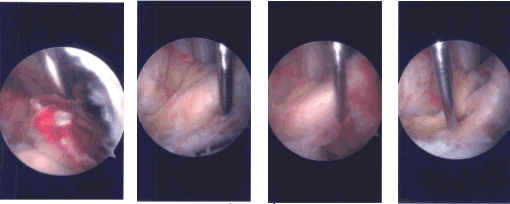

Imágenes de artroscopia intraoperatoria